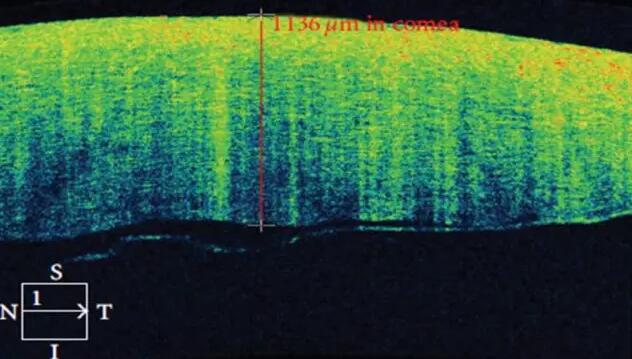

角膜篇

2、角膜厚度评估,角膜水肿、瘢痕、混浊、溃疡、异物、炎症、胬肉等断层观察

3、角膜屈光手术后角膜瓣观察、角膜厚度评估等

4、后弹力层角膜内皮移植术(DSEK)、板层角膜移植术、白内障术后内皮层脱落等术后观察